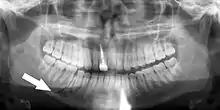

Injuries to supporting bone

This injury involves the alveolar bone and may extend beyond the alveolus.[5][6] There are five different types of alveolar fractures:

Trauma injuries involving the alveolus can be complicated as it does not happen in isolation, very often presents along with other types of tooth tissue injuries.

Signs of dentoalveolar fracture:

- Change to occlusion

- Multiple teeth moving together as a segment and are normally displaced

- Bruising of attached gingivae

- Gingivae across the fracture line often lacerated

Investigation: Require more than one radiographic view to identify the fracture line.

Treatment: Reposition displaced teeth under local anaesthetic and stabilise the mobile segment with a splint for 4 weeks, suture any soft tissue lacerations.